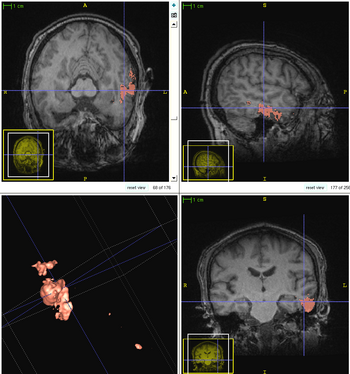

We propose a multi-modal image segmentation framework for longitudinal TBI images. The framework is initialized through manual input of primary lesion sites at each time point, which are then refined by a joint approach composed of Bayesian segmentation and construction of a personalized atlas. The personalized atlas construction estimates the average of the posteriors of the Bayesian segmentation at each time point and warps the average back to each time point to provide the updated priors for Bayesian segmentation. The difference between our approach and segmenting longitudinal images independently is that we use the information from all time points to improve the segmentations. Given a manual initialization, our framework automatically segments healthy structures (white matter, grey matter, cerebrospinal fluid) as well as different lesions such as hemorrhagic lesions and edema. Our framework can handle different sets of modalities at each time point, which provides flexibility in analyzing clinical scans.The segmentation of acute and chronic images using our framework are presented in the following figures. This work has been submitted to SPIE Medical Imaging 2012 [1].

1

2